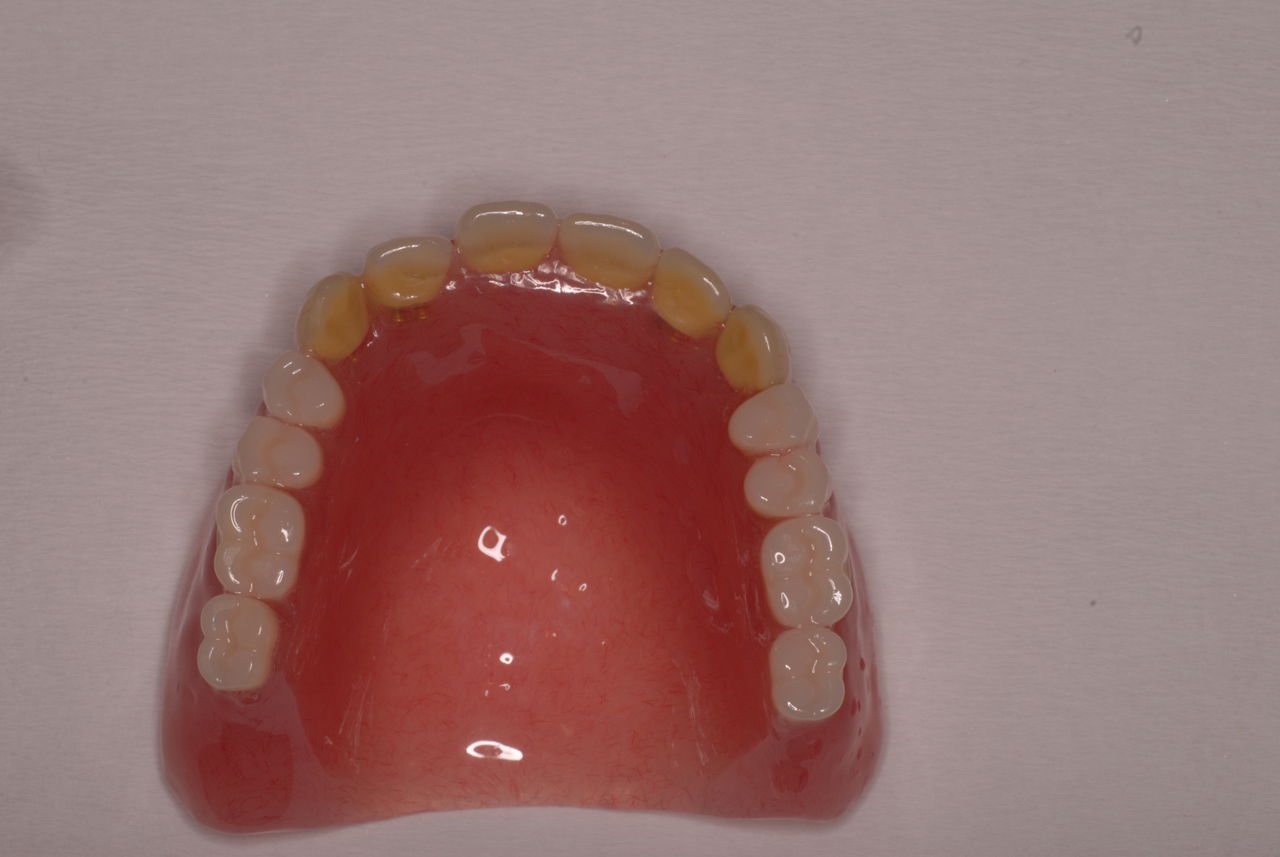

金属にもかかわらず適合が悪い為にプラスチックを重ね着した為に厚くなりしゃべりにくくなっていました。

かなり分厚い入れ歯です。

外注で完成させた入れ歯です。

違いは歯の位置です。あまりに外側で噛むと動くから噛めないのです。